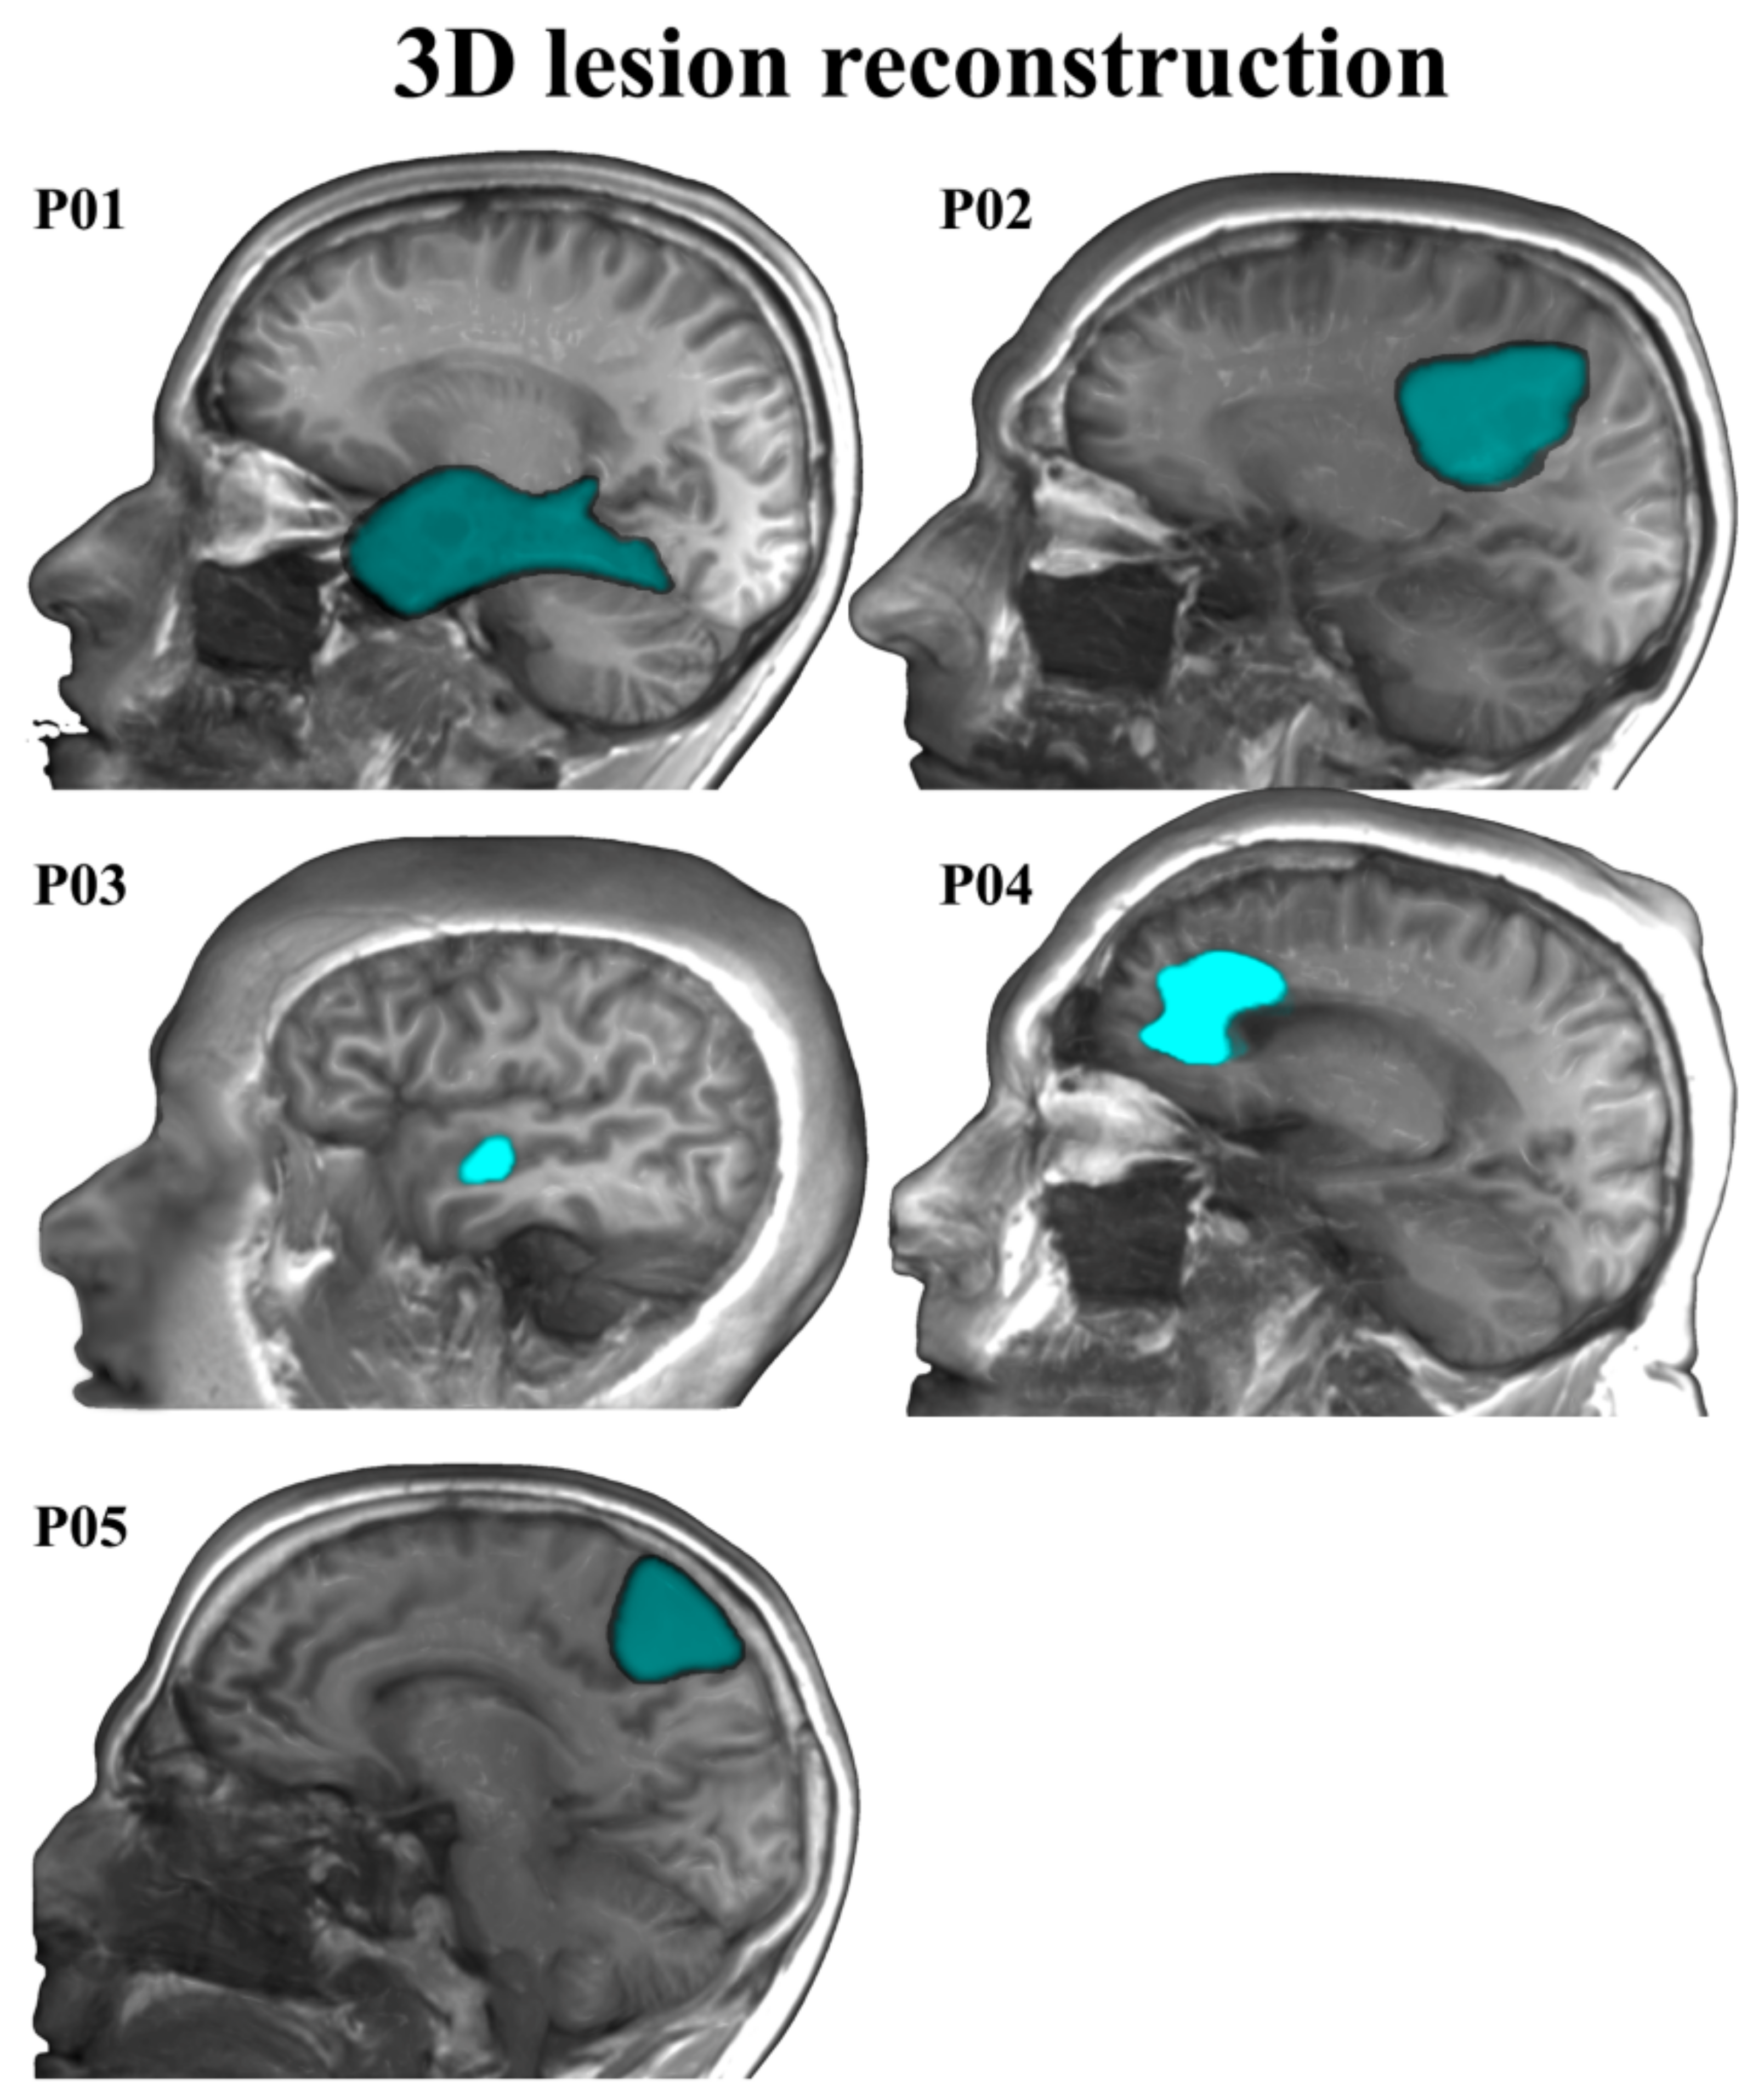

| Patients | Age | Gender | Studies (Years) | Tumor Location | L1 Proficiency | L2 Proficiency | MMSE | Karnofsky Index |

|---|---|---|---|---|---|---|---|---|

| 01 | 22 | Male | 14 | Fusiform | 95.38 | 92.31 | 30 | 90 |

| 02 | 47 | Male | 20 | Cingulate | 100 | 69.23 | 30 | 90 |

| 03 | 41 | Male | 20 | Parietal | 100 | 96.92 | 29 | 90 |

| 04 | 56 | Male | 12 | Frontal | 98.46 | 90.77 | 28 | 90 |

| 05 | 23 | Male | 16 | STS | 100 | 95.38 | 30 | 90 |